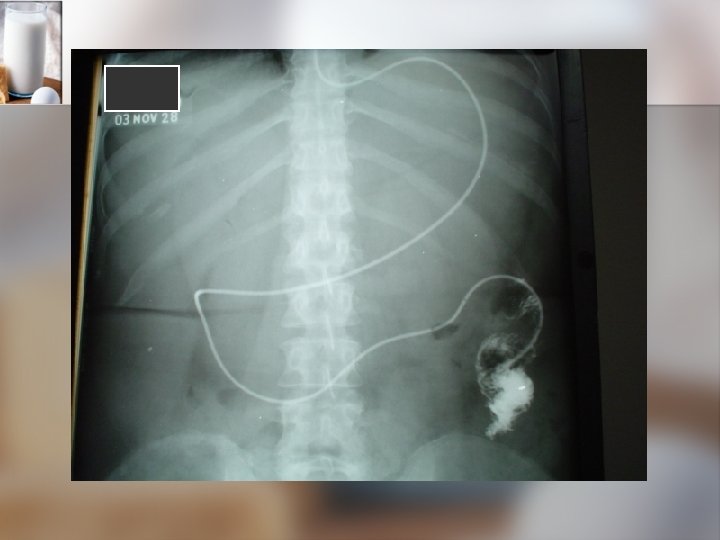

VIAS DE ADMINISTARCION DE NUTRICION ENTERAL Estado de conciencia y riesgo de aspiraciòn n Comodidad del paciente n Condiciones de absorción y patología gastrointestinal. n Duración del tratamiento n Tipo de fórmulas n CINC – FELANPE 2002

Indicaciones para la NPT n n n n TGI no es accesible o funcional. Pacientes con obstrucción intestinal. Ileo Enterocolitis necrotizante. Enfermedad inflamatoria complicada. Pancreatitis severa. Síndrome de intestino corto Otros.